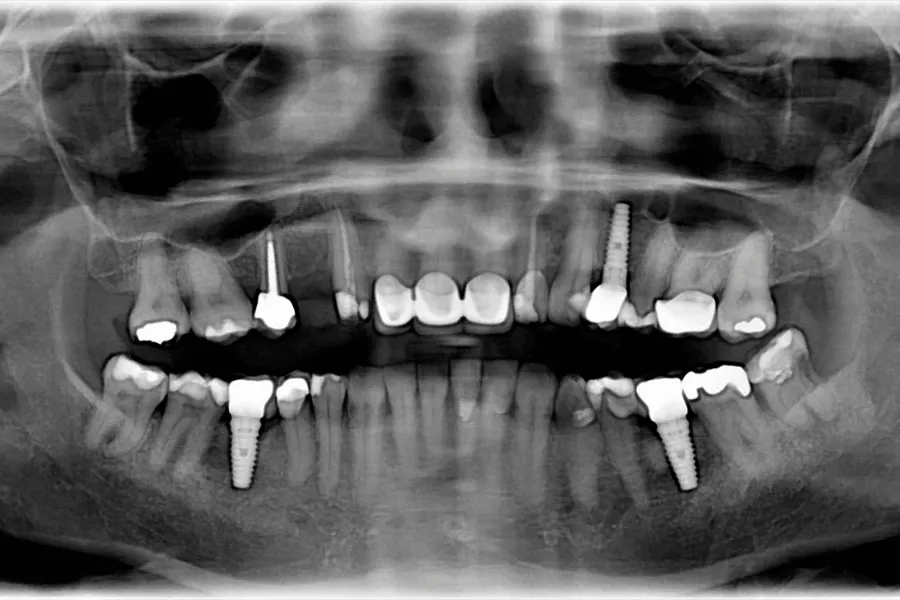

RTG, jeśli są wątpliwości co do stanu kości

Zdjęcie RTG wykonuje się, gdy:

• objawy są niejednoznaczne

• kieszonki wydają się głębsze

• występuje lokalna tkliwość

• istnieje podejrzenie wczesnej utraty kości

Celem RTG nie jest diagnoza samego mucositis, ale wykluczenie początku peri-implantitis.

Kontrola RTG co 12 - 24 miesiące

RTG to jedyny sposób, aby ocenić, czy kość wokół implantu:

• jest stabilna

• ulega stopniowej resorpcji

• wykazuje pierwsze oznaki peri-implantitis

Zdjęcie wykonuje się:

• co 12 miesięcy u pacjentów z podwyższonym ryzykiem

• co 24 miesiące u pacjentów o stabilnych wynikach

RTG często wykrywa początki utraty kości, zanim objawi się ona klinicznie.